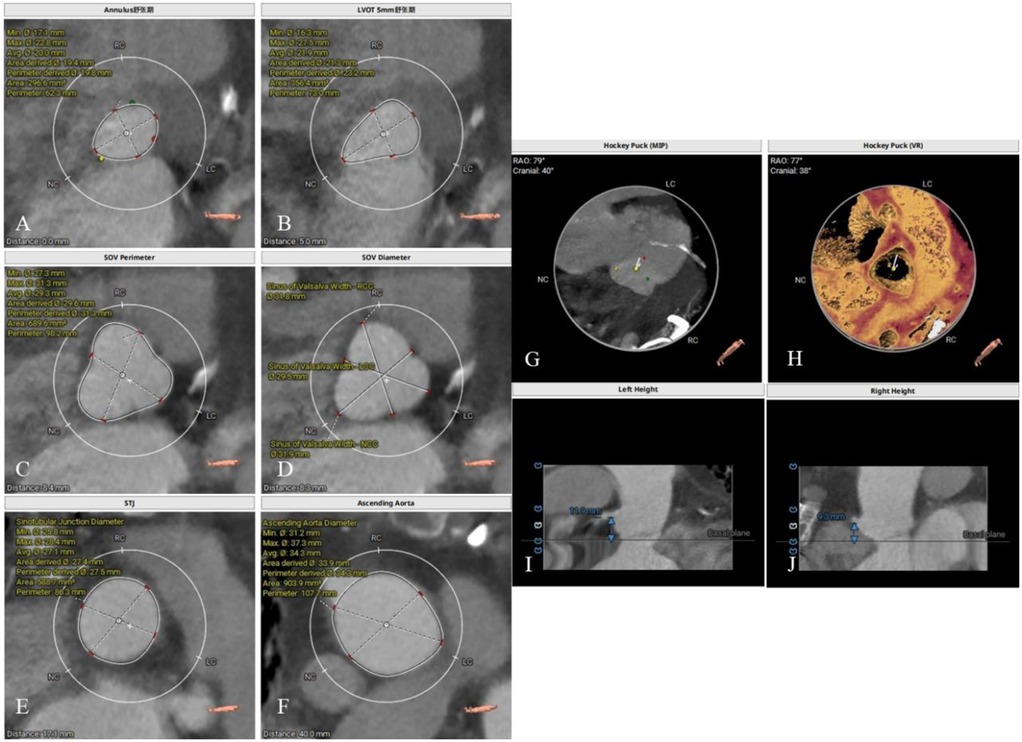

Figure 4

Intraoperative transesophageal echocardiography monitoring. (A) No paravalvular leak on short-axis view; (B) long-axis view indicates adequate valve depth, no impairment of anterior mitral leaflet function; (C) ultrasound color Doppler shows no aortic regurgitation.

Follow-up

At the 1-month follow-up, the patient's symptoms had markedly improved (NYHA functional class II). Transthoracic echocardiography demonstrated normal morphology and function of the prosthetic valve, with no evidence of late prosthesis migration, and spectral Doppler imaging revealed no regurgitation (Figure 5). LVAD parameters remained stable throughout the follow-up period (pump speed 2,200–2,300 rpm, flow approximately 2.5 L/min).

Figure 5

One-month postoperative echocardiographic follow-up. (A) Spectral Doppler showing no evidence of aortic regurgitation; (B) long-axis view demonstrating no late prosthetic valve migration.